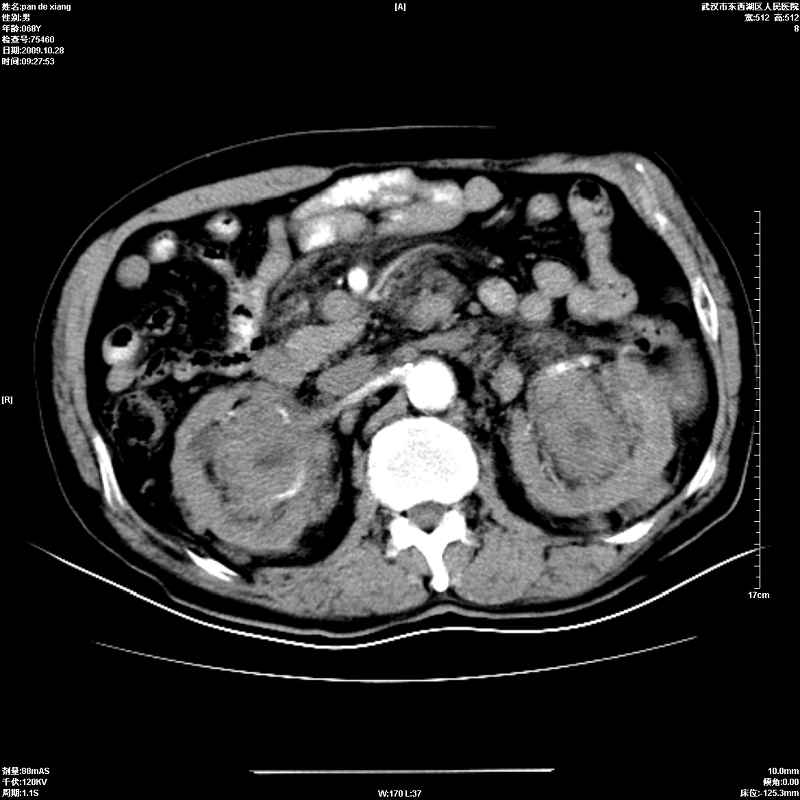

以下是引用杀毒软件在2009-10-28 20:41:00的发言:[br]结合临床考虑---白血病双肾改变或淋巴瘤。

以下是引用zxl51642在2009-10-29 9:59:00的发言:[br]结合临床“单克隆免疫球蛋白血症”,考虑双肾为继发损害并肾功能不全(尿中大量igg及少量iga、igm等大分子免疫球蛋白滤出所致继发损害),椎前软组织肿块为髓外造血。与浆细胞瘤有区别,平扫时有战友说的很清楚。